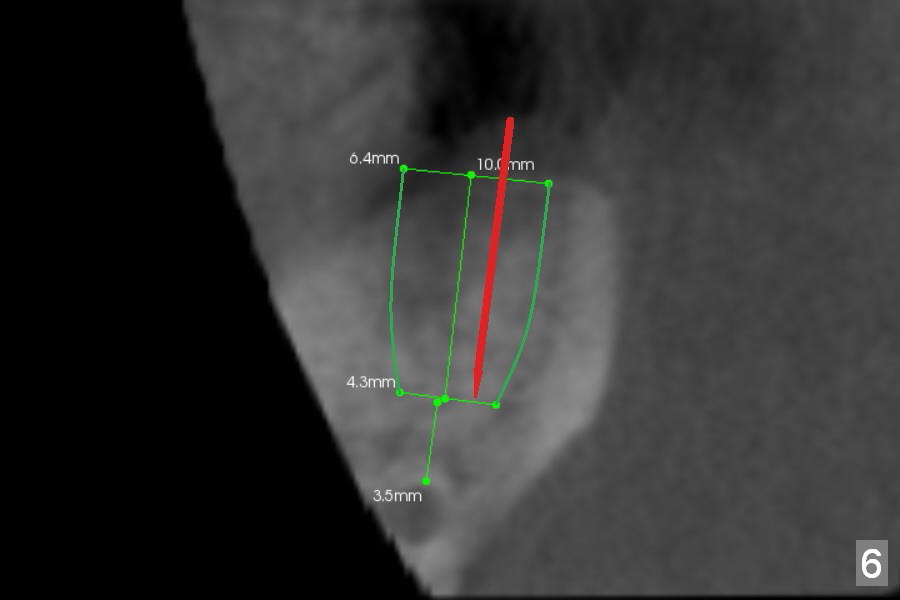

Preop CBCT shows that a 6.4x10 mm implant is appropriate if placed in the middle of the socket (septum), 6 mm from the crown of #30 (Fig.5). Coronal section confirms that because of the lingual slope of the socket, osteotomy should be placed lingually (Fig.6 red line). Three-D image is shown in Fig.7.